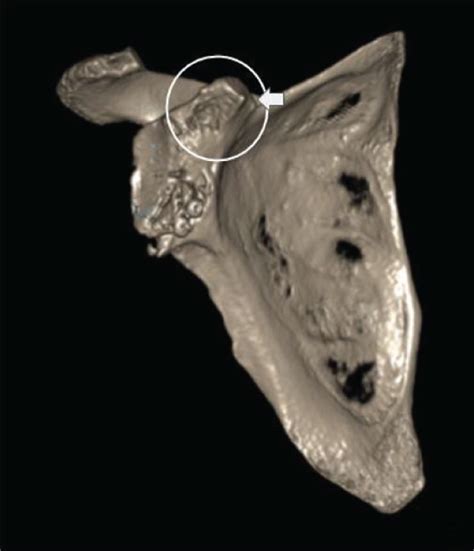

Alright, let’s start with the basics. A coracoid scapula CT scan is a type of medical imaging test that uses X-rays to create detailed, cross-sectional images of your shoulder. Specifically, it focuses on two key parts: the coracoid process and the scapula. The scapula, or shoulder blade, is that large, triangular bone on your back. The coracoid process is a small, hook-like projection on the front of the scapula. This scan provides doctors with a comprehensive view of these structures, allowing them to diagnose a wide range of conditions. So, basically, it’s like taking a super-detailed photo of that part of your shoulder. Think of it as a virtual tour that helps doctors see what’s going on inside without having to make any incisions. Pretty cool, huh?

This scan utilizes a sophisticated piece of equipment known as a computed tomography (CT) scanner. The scanner rotates around your body, taking multiple X-ray images from different angles. These images are then processed by a computer to create detailed, three-dimensional representations of the coracoid process, scapula, and surrounding tissues. The level of detail provided by a CT scan is far superior to that of a standard X-ray. It allows doctors to see subtle fractures, dislocations, or other abnormalities that might be missed by other imaging techniques. Therefore, it’s a valuable tool in diagnosing shoulder problems and guiding treatment decisions. Imagine being able to zoom in and examine every nook and cranny of your shoulder – that’s essentially what a CT scan does. With its ability to visualize bone and soft tissues, such as muscles, ligaments, and tendons, it is capable of providing a wealth of information to medical professionals.

Now, you might be wondering, why the coracoid process? This small projection plays a crucial role in shoulder function. It serves as an attachment point for several important muscles and ligaments, including the biceps tendon, the coracobrachialis muscle, and the coracoacromial ligament. Any damage or abnormality in this area can significantly impact shoulder movement and cause pain. That’s why a CT scan focusing on this area is so useful in identifying potential issues. It helps doctors pinpoint the exact location and nature of the problem, allowing them to provide the best possible care. Understanding this anatomy and the importance of the coracoid process helps appreciate the scan’s significance in diagnosing and treating shoulder-related conditions. So next time you hear someone talking about a shoulder injury, remember the coracoid process – it’s more important than it looks!